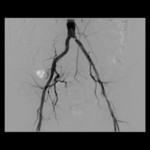

Zu den angebotenen Untersuchungsverfahren gehören vor allem Gefäßdarstellungen aller Körperregionen.

• Ballon-Angioplastie (PTA)

• der peripheren Gefäße,

• der Nieren- und

• Abdominalarterien,

• der Hals- und

• Kopfgefäße sowie